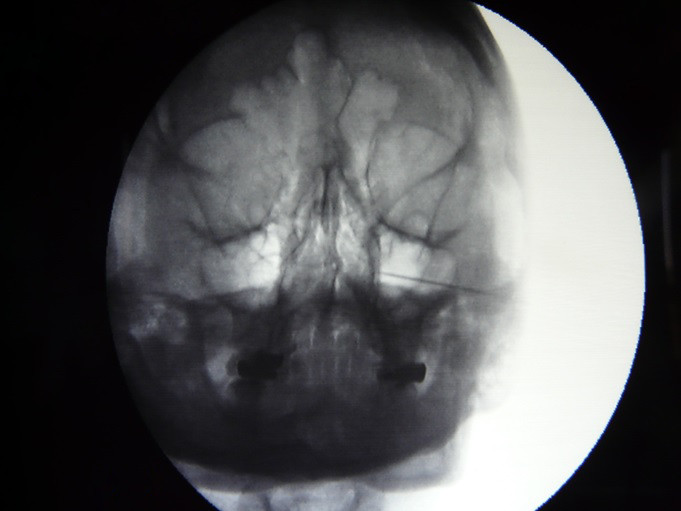

Fig.6. El paciente se coloca en posición decúbito supino, y en proyección lateral el fluoroscopio emite su haz de rayos a la base del cráneo, se alinean las ramas horizontales y verticales mandibulares para que estén en un mismo plano, esto es fundamental para superponer las dos fosas Pterigomaxilares y puedan visualizarse como una sola, y no se fije una falsa diana, visualizando la fosa del lado contrario y tomarla de forma equivocada.

Se emplea anestesia local que permita la introducción de aguja, electrodo o crio sonda.